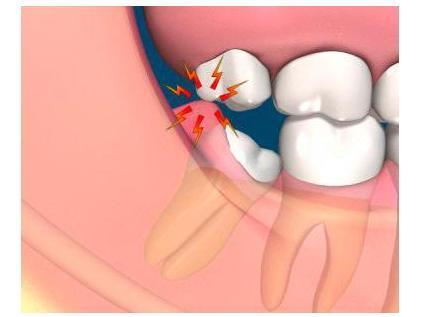

Os dentes do siso são chamados assim porque costumam doer desde que começam a sair, ao redor dos 16 anos, até que acabam de o fazer, às vezes até 10 anos depois. Devido à mudança da dieta dos humanos há uns 5000 anos atrás ou mais, existe uma tendência de um crescimento menor das mandíbulas, dificultando ainda mais o crescimento dos dentes, que muitas vezes devem ser extraídos já que amontoam para à frente (em 44% dos casos) ou não saem completamente pela gengiva (38% dos casos).

A extração dos dentes do siso pode ser realizada devido a vários fatores, mas é preciso observar sempre o impacto que teve ou pode ter em uma dentadura. O principal motivo é o desvio dos dentes anteriores, seguido de problemas de cáries devido à dificuldade gerada para escovar um dente sem ter saído completamente; é por isso que a extração sempre será objeto de uma profunda análise por parte do odontólogo. A extração dos dentes não costuma ser dolorosa, mas deve considerar alguns detalhes para não ter nenhuma surpresa. Neste artigo de umComo conhecerá mais sobre o assunto e sobre o cuidado da sua boca quando já tiver retirado o dente.